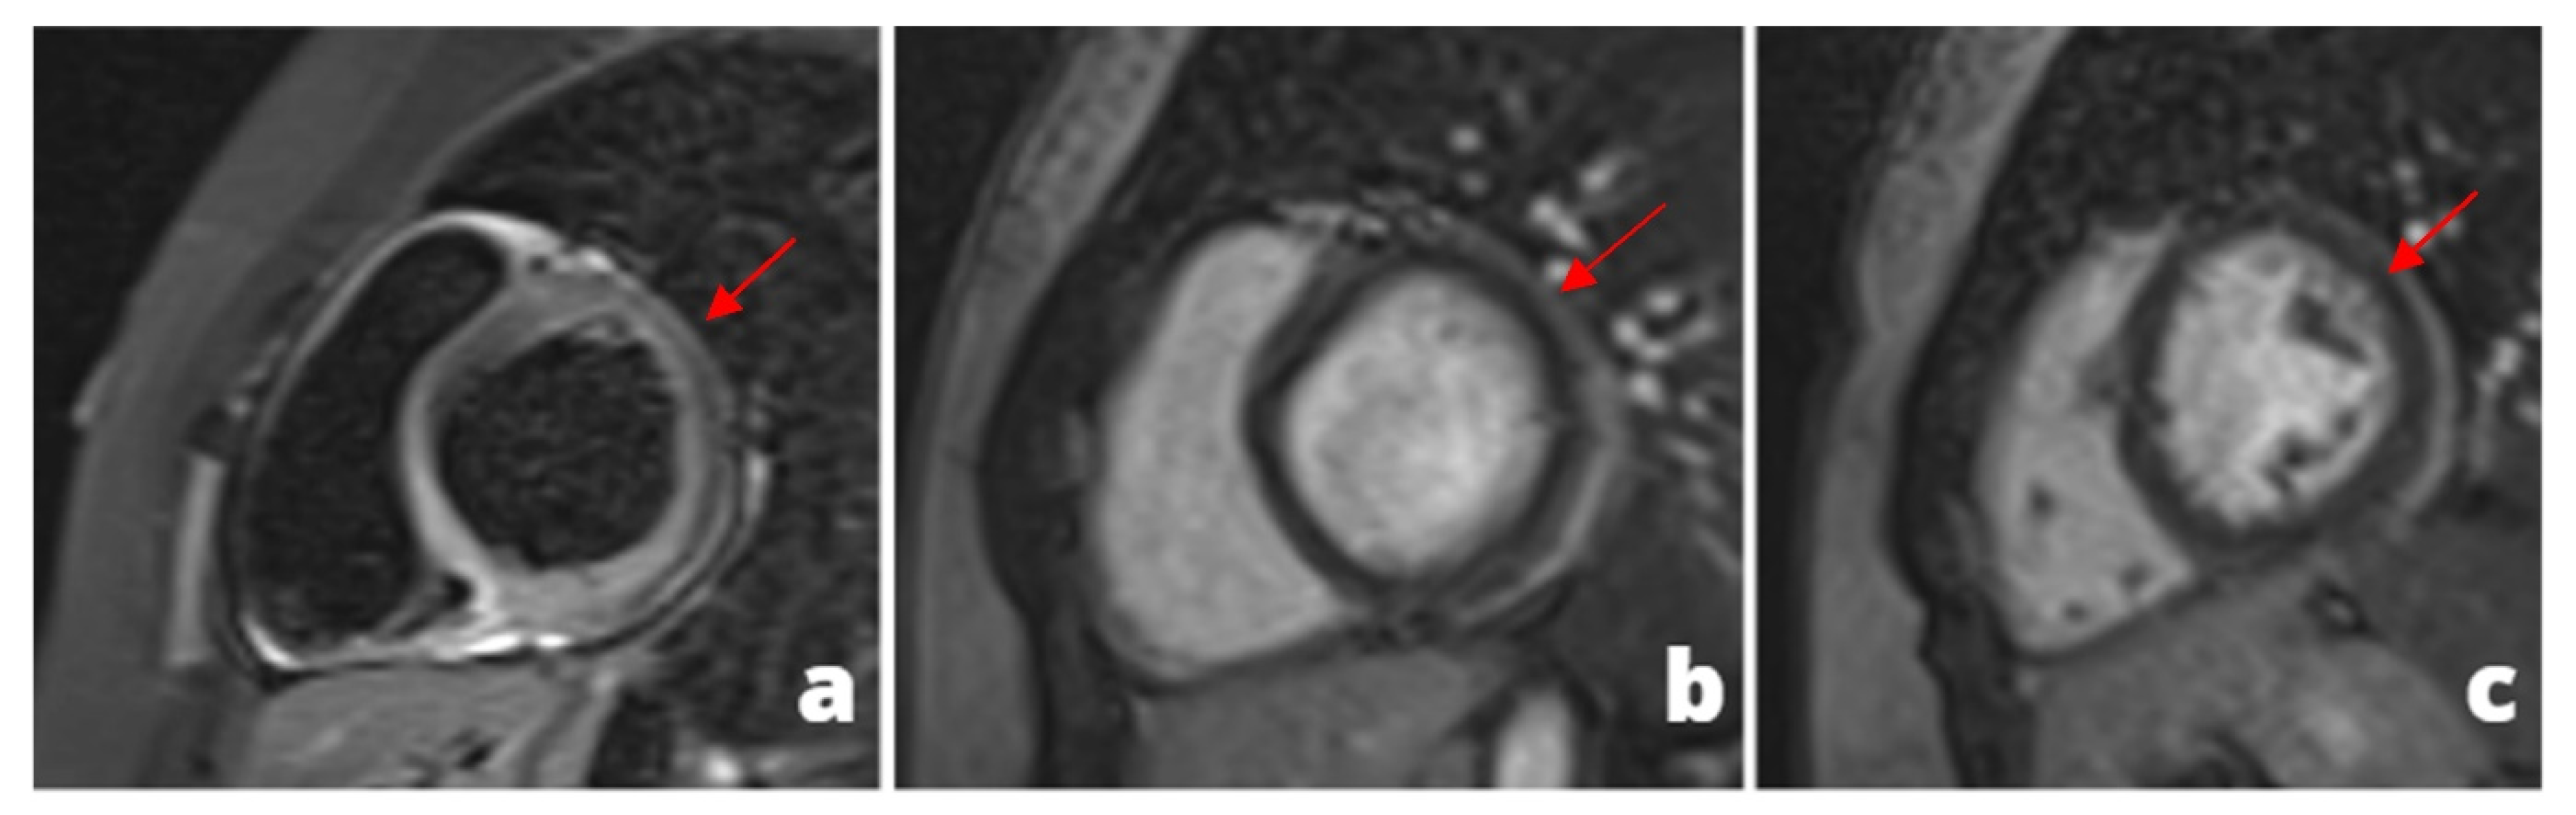

Figure 3. MINOCA-Miocardial Infarct non obstructive coronaries. The patient presented to the emergency department with acute chest pain, ECG and cardiac enzymes suggestive of STEMI in the lateral wall of the left ventricle. The patient was readily referred to coronary angiography and cardiac catheterization showed absence of obstructive stenoses in the coronary tree (a). One day later a cardiac MRI was performed demonstrating a subacute ischemic scar in the lateral wall of the medium-apical left ventricle ((b)-LGE short axis view, (c)-LGE four chambers view). In the context of transmural late gadolinium enhancement, a constantly hypointense central area is present, representing a microvascular obstruction zone (red arrow). A cardiac CT was subsequently performed in order to assess coronary wall features and the presence of atherosclerosis. CT images in volume rendering (d) and multiplanar oblique reconstruction (e) demonstrated a non-calcified atherosclerotic alteration in an obtuse marginal vessel, serving the infarcted zone. A partly calcified atherosclerotic pathology was present in the anterior descending artery.